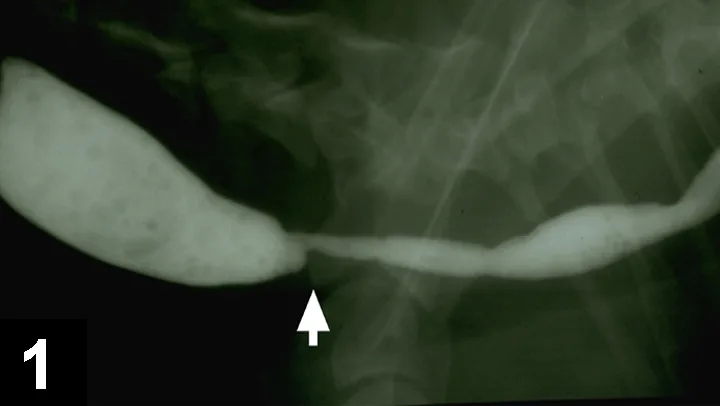

The most likely cause of this abnormality is an intramural esophageal stricture. Unlikely causes for esophageal narrowing include extrinsic extraesophageal compression from neoplasia or inflammation, vascular ring anomaly, presence of an esophageal foreign body, or esophageal neoplasia. Endoscopy was done to delineate the obstruction and to perform therapeutic esophageal dilatation. Figure 2 shows the esophageal narrowing at the thoracic inlet. Figure 3 shows the esophagus following a balloon dilatation procedure.

Figure 2. Endoscopic view showing a benign focal esophageal stricture secondary to a doxycycline tablet in a cat